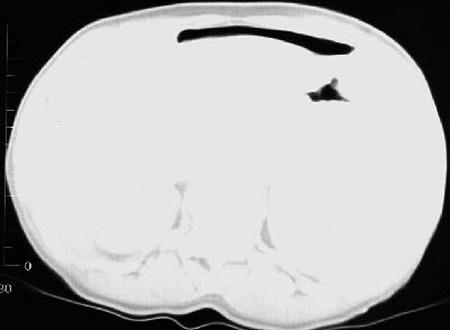

问题 男,44岁,突然中上腹痛,压痛,反跳痛,腹肌紧张,发热,白细胞计数升高,CT检查如图,最可能诊断是 ( )

选项 A.急性胰腺炎 B.慢性胰腺炎 C.胃小弯溃疡穿孔 D.胰腺癌 E.胃癌

答案 C